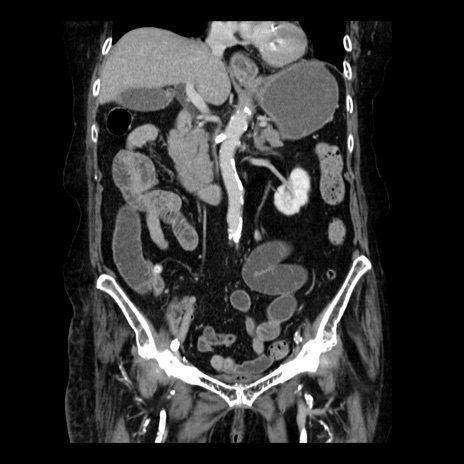

症例14(冠状断像)

【症例】 90歳代女性

【主訴】 腹痛・嘔吐

【現病歴】今朝から左側腹部痛を認めた。 経過観察していたが、嘔吐を認めたため来院。

【既往歴】 子宮癌術後

【身体所見】 意識清明、BP 127/54mmHg、P 98bpm Sp02 95%(RA)、BT 35.8°C、腹部平坦・軟腸ぜん動音聴取良好、右下腹部圧痛(+) 反跳痛なし

【データ】WBC 9800、CRP 0.46

横断像